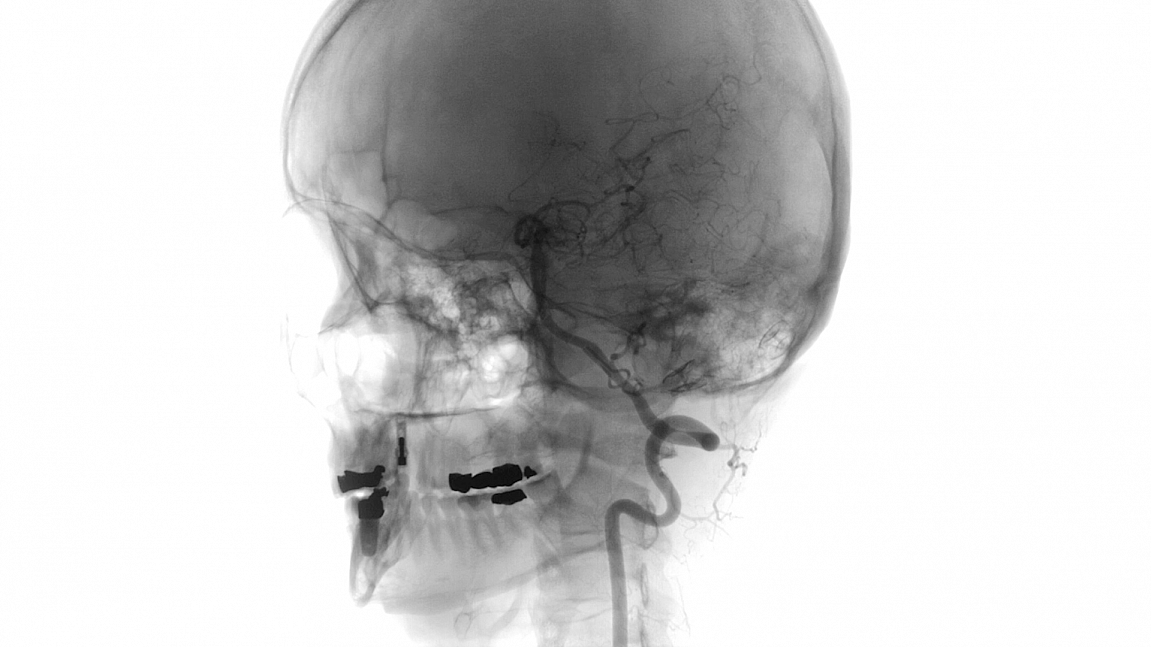

„Gibt es ein Leben nach dem Tod? Wenn nein, was sagt die Rentenversicherung dazu?“ Sobo Swobodnik nimmt uns mit auf eine albtraumhafte Reise: Von dem Tag an, als bei ihm durch Zufall ein Hirnaneurysma entdeckt wurde, bis zum Tag der OP. Gleich zu Beginn erzählt der Filmemacher: „Das ist mein Gehirn. Ich gebe zu, ich könnte es stundenlang betrachten.“ Auf diese Worte hin begleiten wir ihn zwei traumatische Monate lang. Zu Ärzt.innen, Freunden und dem neuen Psychiater, immer in Begleitung des Bastards im Hirn, der seinen schlagartigen Tod bedeuten könnte. Die collagenhaften Bilder, begleitet von Swobodniks Stimme und verstärkt durch die musikalische Komposition von Elias Gottstein machen den Film zu einer visuellen Hörerfahrung im besten Sinne. Janna Lihl